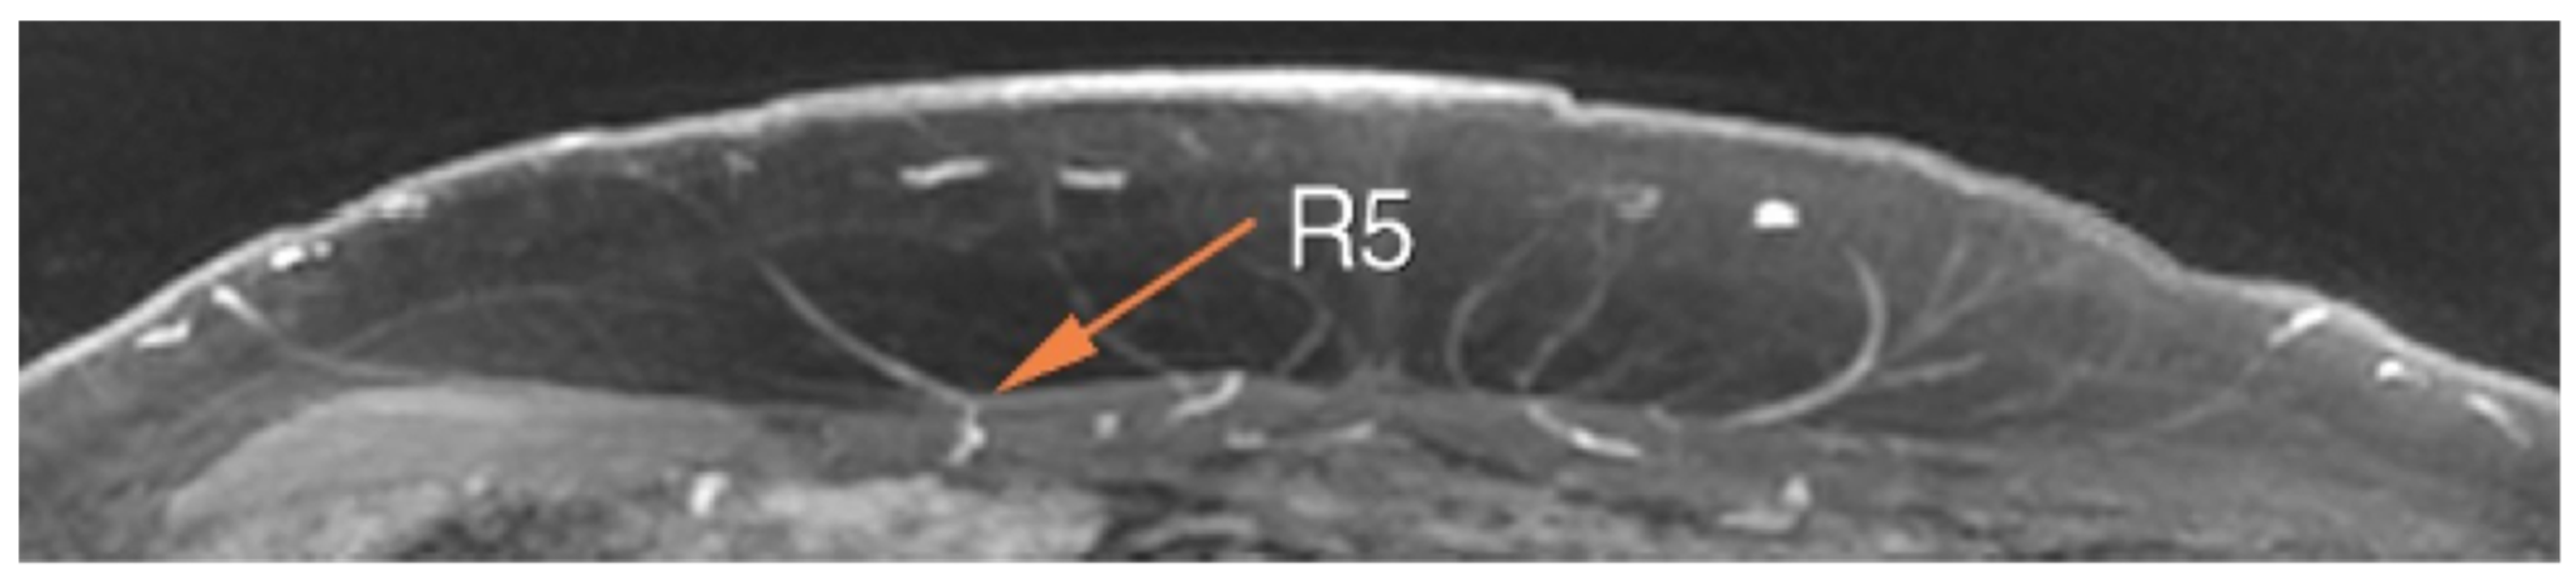

4. Magnetic Resonance Angiography (MRA)